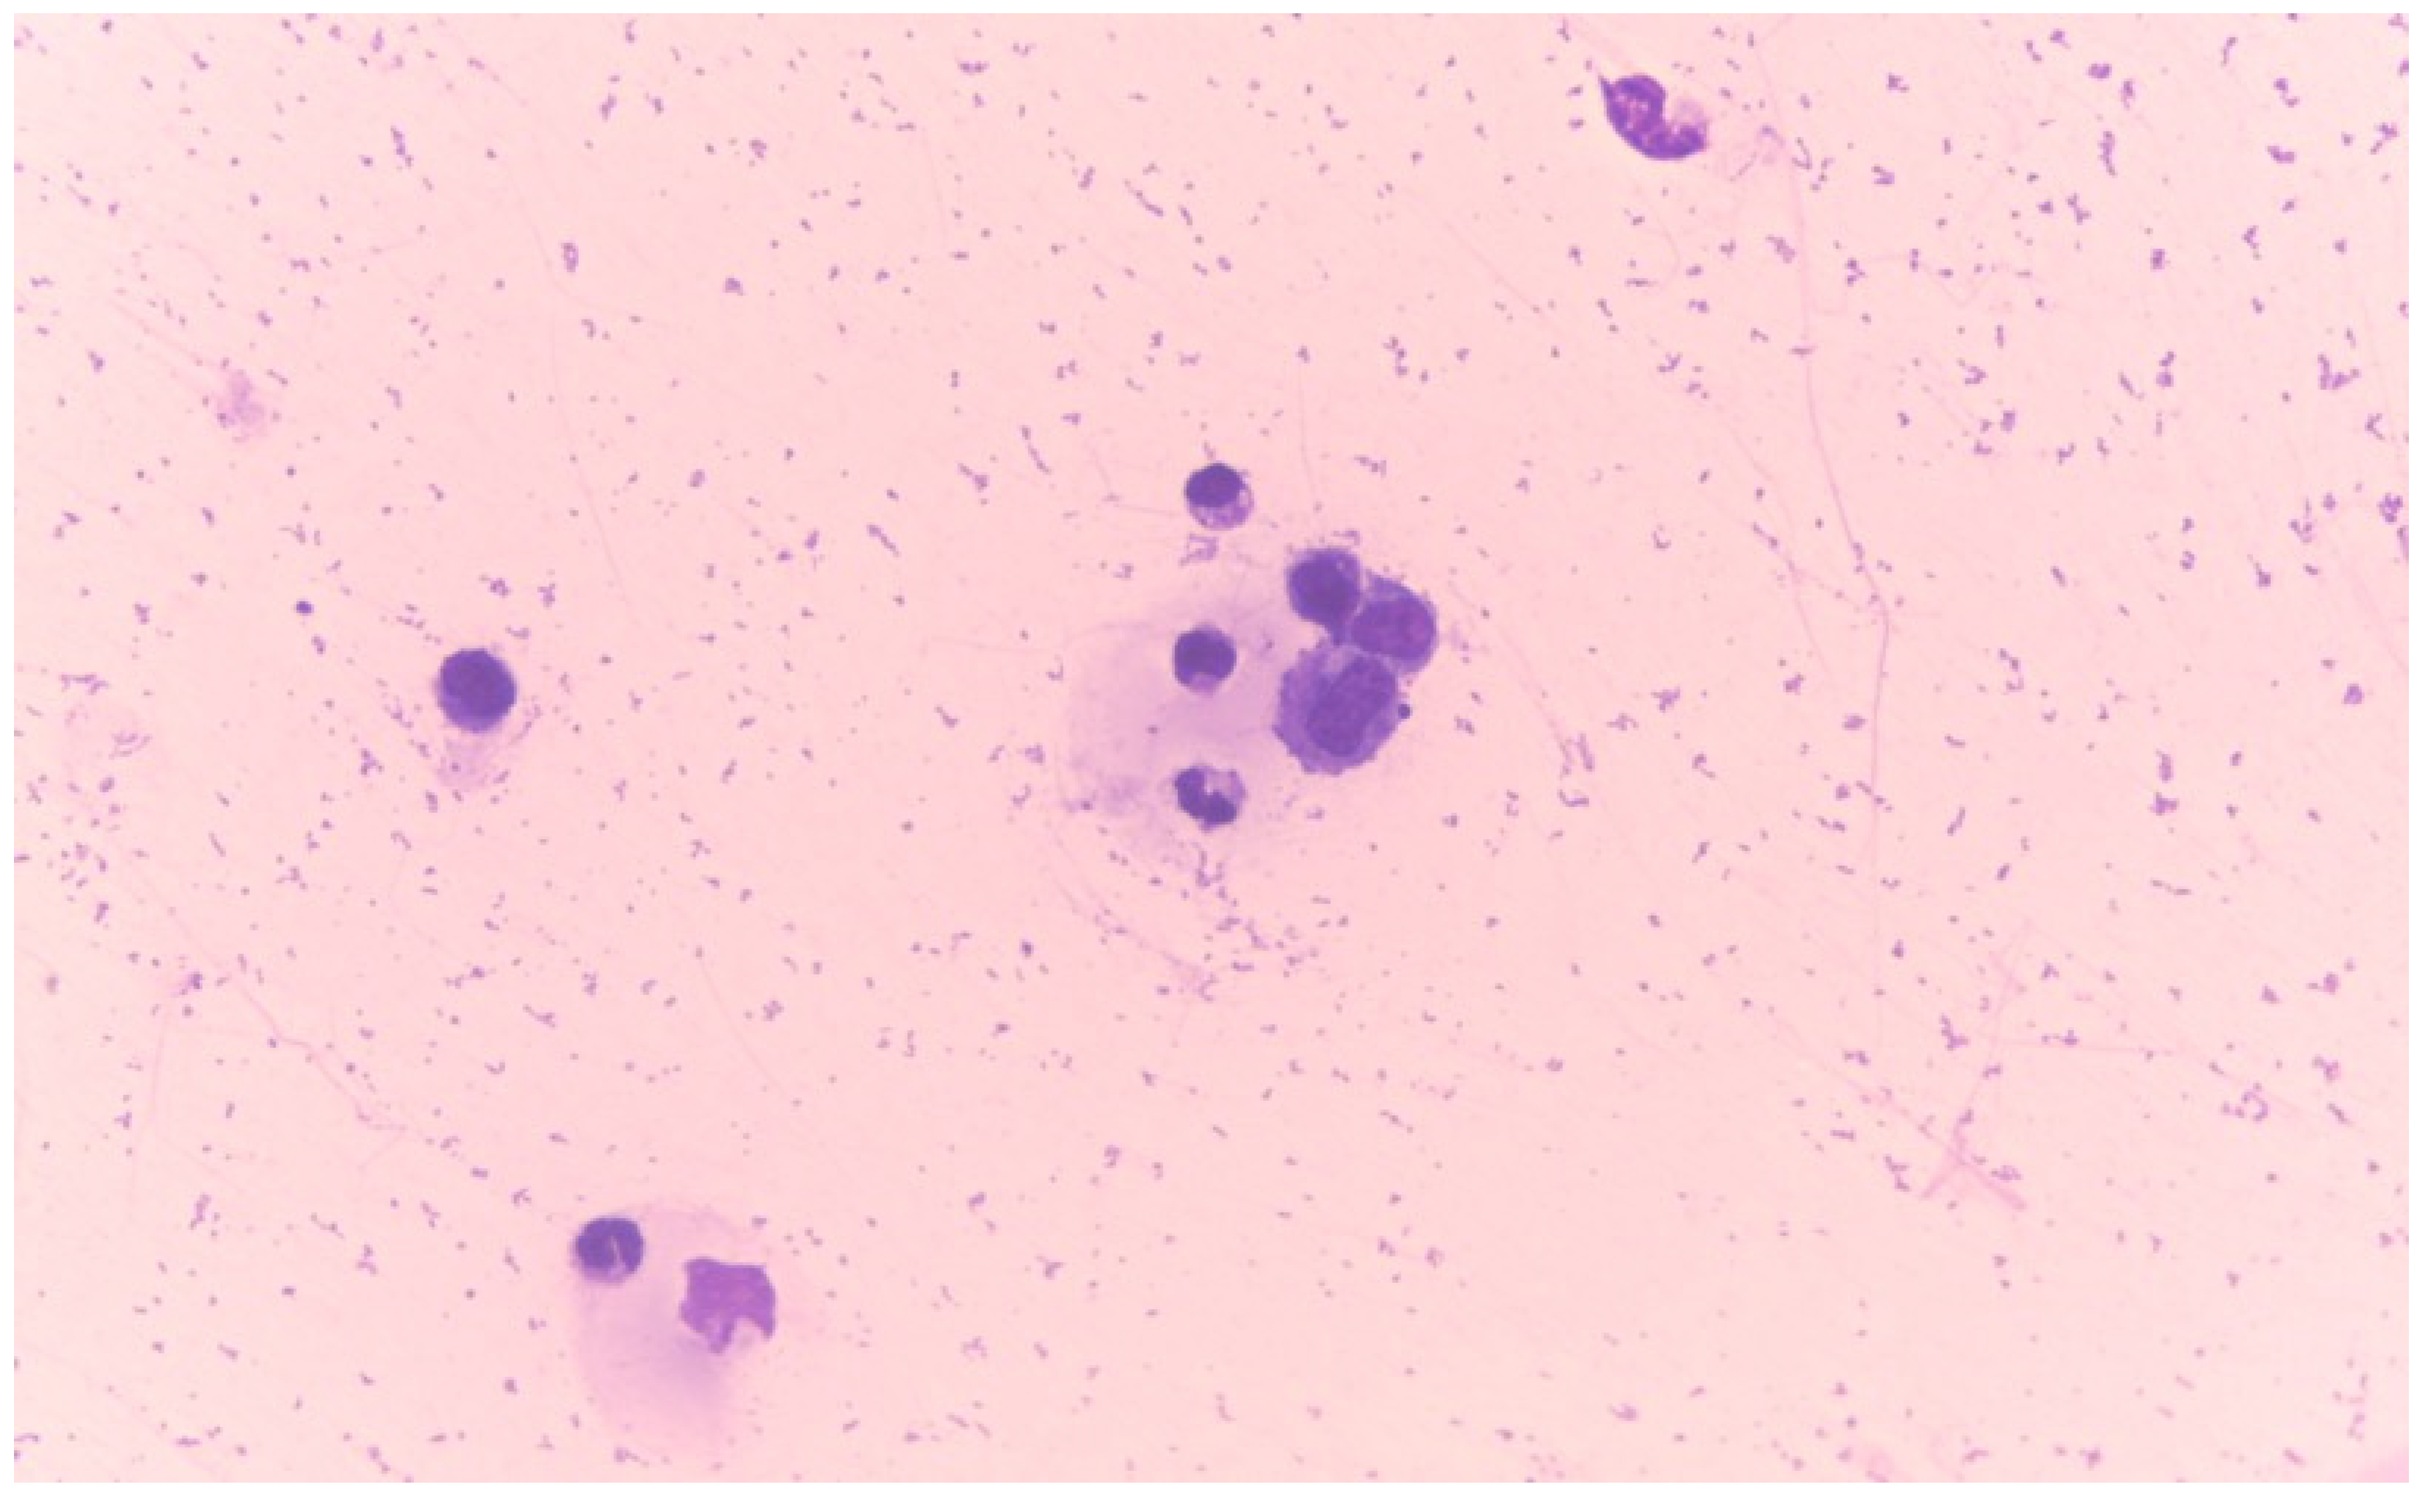

- Fonte-Oliveira, L.; Lopes, C.; Malhão, F.; Canadas-Sousa, A.; Gregório, H.; Marcos, R.; Santos, M. The utility of the cell tube block technique in the diagnosis of effusive feline infectious peritonitis. In Proceedings of the Congress of European Society of Veterinary Clinical Pathology (ESVCP/ECVCP), University of Veterinary Medicine, Budapest, Hungary, 28–31 August 2024; p. 148. [Google Scholar]